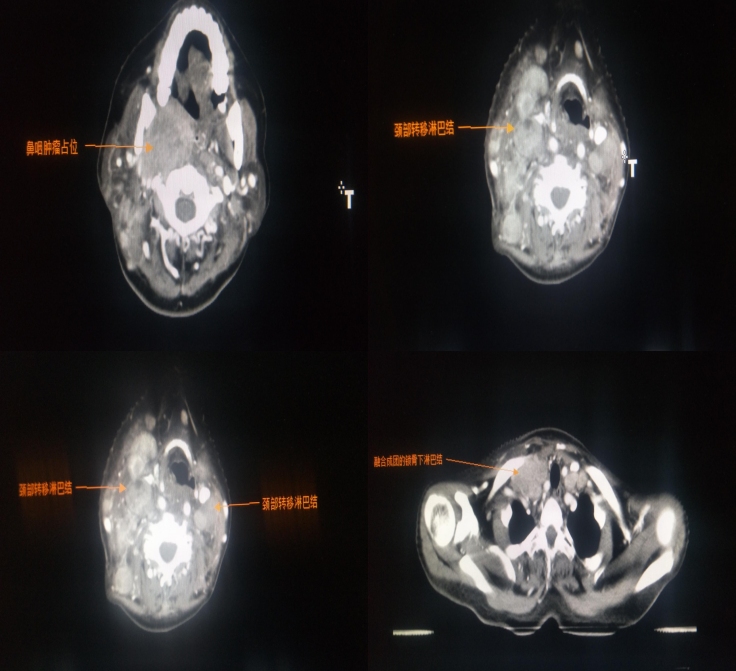

2020年6月16日放疗定位,CT示右侧咽隐窝及咽后壁见巨大软组织肿块影,邻近颞骨岩部、枕髁、翼内板、翼外板、蝶窦后壁骨质破坏,双侧颌下、下颌下、耳前、耳后及颈部、右侧锁骨上、锁骨下多处淋巴结肿大。

初步诊断:

鼻咽鳞状细胞癌 未分化型;

侵犯颅底、颞部脑膜、右侧翼腭窝、右侧腮腺

侵犯II、III、IV、VI颅神经

双侧颈部淋巴结转移

右侧锁骨上、锁骨下淋巴结转移

诊断分期:cT4N3M0 IVb期